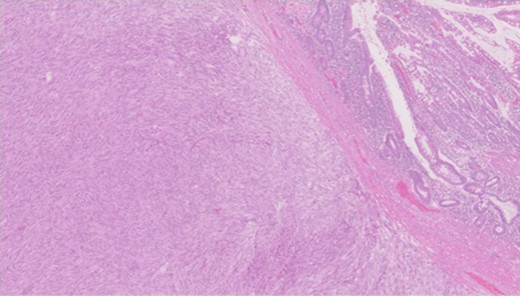

Pathology—GIST of spindle cell type (Figs 3 and 4), 90 mm in size, with complete local excision. Mitotic count—3 per 5 mm square. CD117 (Fig. 5) and DOG1 (Fig. 6) positive staining giving a prognostic group of moderate risk (Miettinen’s classification) of progressive disease. It is widely accepted that Interstitial Cells of Cajal (ICC) are pace maker cells of the gut and probable progenitor cells of GIST. Hyperplasia of ICC can be seen in cases with NF1, however, in this case this could not be shown in the background bowel (Fig. 7).

Higher power view showing the spindle appearance of tumour cells.